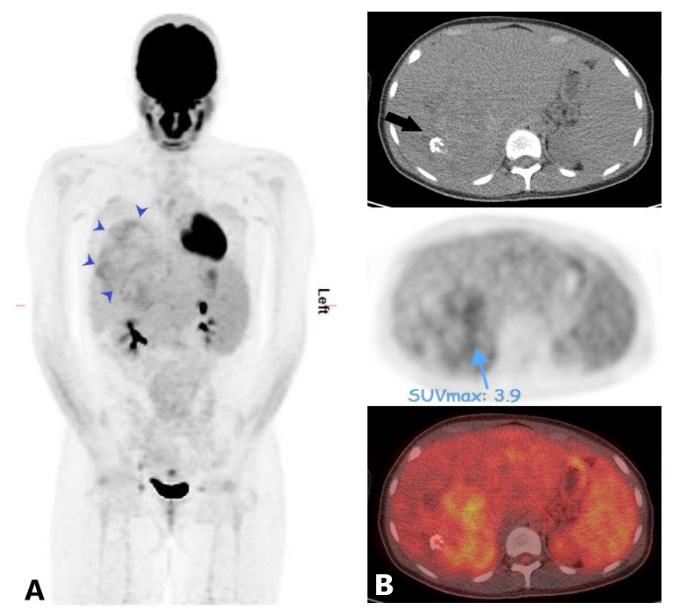

Liver biopsy confirmed the diagnosis of sclerosing epithelioid fibrosarcoma. F-FDG PET CT scan for initial staging showed mild to moderate uptake throughout the hepatic mass without evidence of distant metastatic disease (Figure 4). Subsequently, the patient underwent an orthotopic liver transplant. On the most recent surveillance imaging, 24 months after transplantation, no findings of disease recurrence were identified, and serum CA 19-9 remained normal.

Figure 4. Maximum intensity projection (MIP) of FDG PET (A) shows mild to moderate uptake within the hepatic mass (blue arrow heads) and otherwise normal biodistribution of the tracer throughout the body with no PET findings of distant metastasis. Fused axial images of FDG PET and CT scan (B) show the most FDG avid areas of the mass. Note a focus of calcification in the mass on the non-contrast CT scan image (arrow).